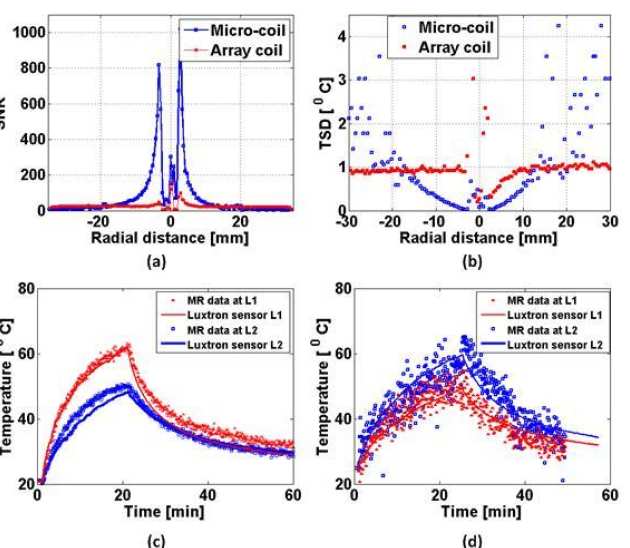

Evi Kardoulaki, Richard Syms, Ian Young, Marc Rea and Wady Gedroy

We have investigated whether local flexible micro-coils integrated with ablation catheters can improve the temperature accuracy during MR-thermometry in liver laser interstitial thermal therapies (LITTs). A liver-mimicking gel phantom was used to assess micro-coil derived image quality and sensitivity and ensure such coils can provide adequate FOV and resolution for the target application at 3T. The impact of liver motion was assessed using a MR-compatible hydraulic motion simulator. The thermal profile of a static phantom during an Nd:YAG laser ablation was monitored using reference-based PRF MR-thermometry and the robustness of the method under respiratory gating was evaluated on an un-heated phantom. The results were compared with the best locally available array coil for LITTs. Micro-coils improve the temperature accuracy by 1.5-10 times in a radius matching typical lesion dimensions and enable 1 mm image resolution. The resolution can be maintained during motion by using short acquisition time sequences while the SNR remains sufficient for accurate MR-thermometry. The temperature error on the un-heated phantom under respiratory gating does not exceed 1oC.

| a) Radial SNR profile of the thermometry baseline image, b) respective radial temperature standard deviation; c) and d) Comparison of MR-inferred transient temperatures with the fluoro-optic readings. |